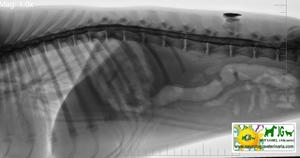

RADIOGRAFÍA SIN CONTRASTES |

RADIOGRAFÍA CON CONTRASTES |